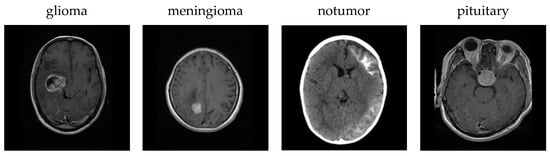

In Figure 6a, each column shows three original MRI images and the class labels predicted by the model for the classes glioma, meningioma, notumor and pituitary, respectively. In (b), the regions that the model takes into consideration when assigning this class label are visualized with Grad-CAM. In the generated heat maps, red and yellow colors indicate the most important regions, while blue and green colors indicate less important regions. In the glioma image, the tumor is usually located in the deep cerebral regions, and this region is clearly highlighted in red on the Grad-CAM maps. This shows that the model can correctly identify the tumor area. In the meningioma image, the model correctly detected the location of the tumor near the dura mater and the activation maps generally showed high focus around the lesion. In the notumor image, the model focused on a wider area and could not highlight a distinct region because there was no tumor. In the pituitary image, the activation of the model was concentrated in the region where the pituitary gland is located, indicating that even small and deep-seated tumors can be successfully localized. These visualizations clearly revealed the regions that should be focused on in the image for each tumor type and that the model not only achieves classification success but also makes decisions by taking into account medically meaningful regions, significantly increasing the interpretability of the model.

Figure 6.

Explainability results. (a) Original images and (b) Grad-CAM visualizations.